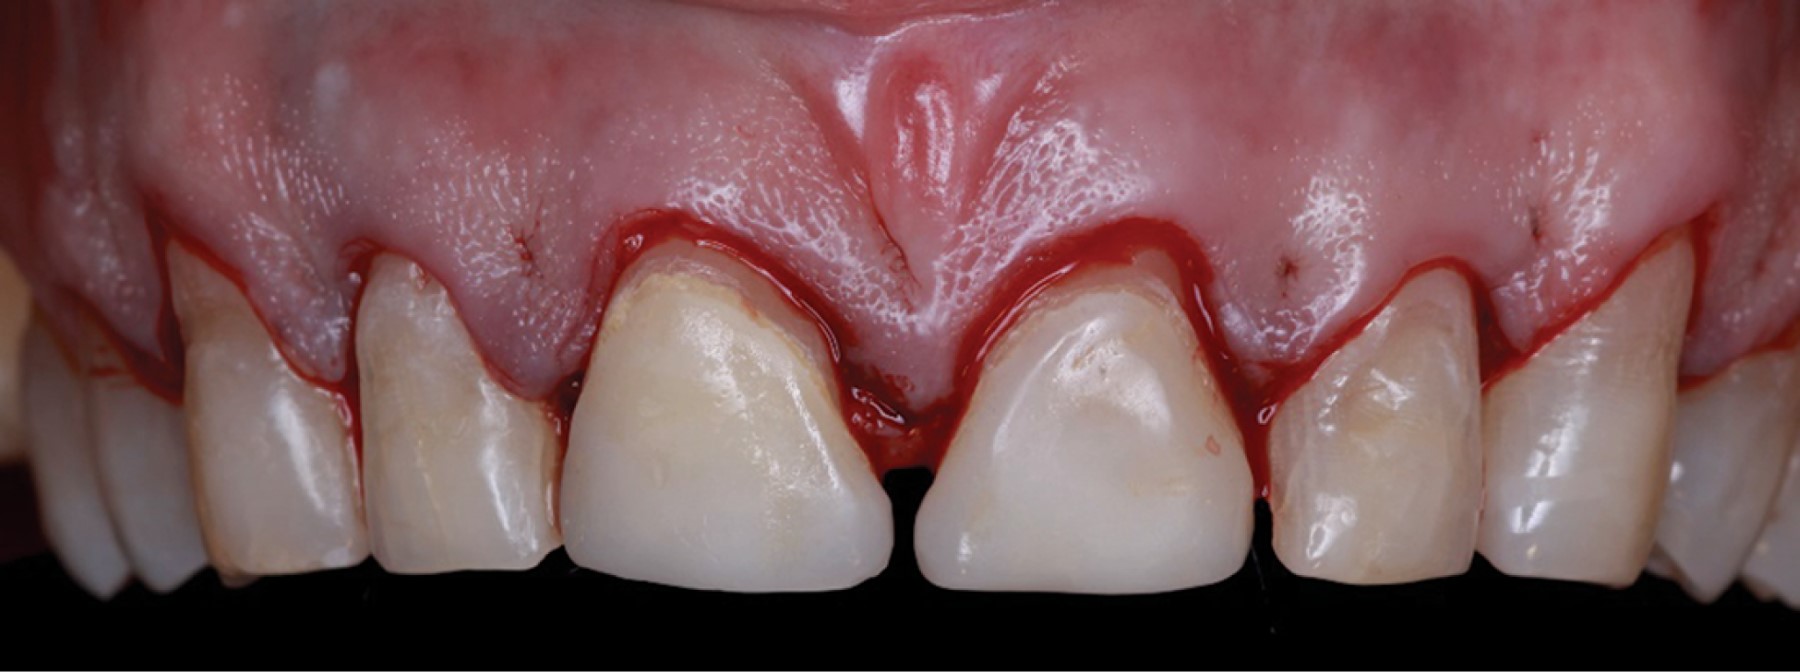

Introduction: crown lengthening for aesthetic purposes aims to reveal an adequate crown length and reduce gingival exposure. The procedure includes gingivectomy and alveolectomy to restore the prosthetically required supracrestal gingival tissue according to physiological dimensions. Through an intraoral scan of the maxilla, mandible, and maximum intercuspidal position, and using specialized software, the shape of the teeth and the gingival contour are digitally designed. This design generates an image of the desired aesthetic restoration for the prosthodontist and periodontist. The physical fabrication of the design is computer-assisted (CAD-CAM), creating a vacuum-formed acrylic resin surgical guide to determine the clinical crown length required in surgery. Objective: the presented interdisciplinary case describes an innovative technique using digital workflow through software that, from an oral scan, digitally designs a Mock-Up used as a guide for periodontal surgery. Case presentation: a 52-year-old ASA I patient attended the Periodontics Master's clinic at Universidad Autónoma de Coahuila (UAdeC) for periodontal surgery with aesthetic purposes. The surgery was performed by placing the Mock-Up in the anterosuperior region as a guide for gingivectomy. Then, a flap was raised before the alveolectomy, considering the length of the supracrestal gingival tissue. Finally, the soft tissues were sutured with a horizontal mattress suture technique. Results: seven days later, the sutures were removed, showing correct and uniform tissue healing. Conclusions: this digital approach offers a significant reduction in surgical time, in addition to satisfactory esthetics and precise gingival architecture.

Figure 4